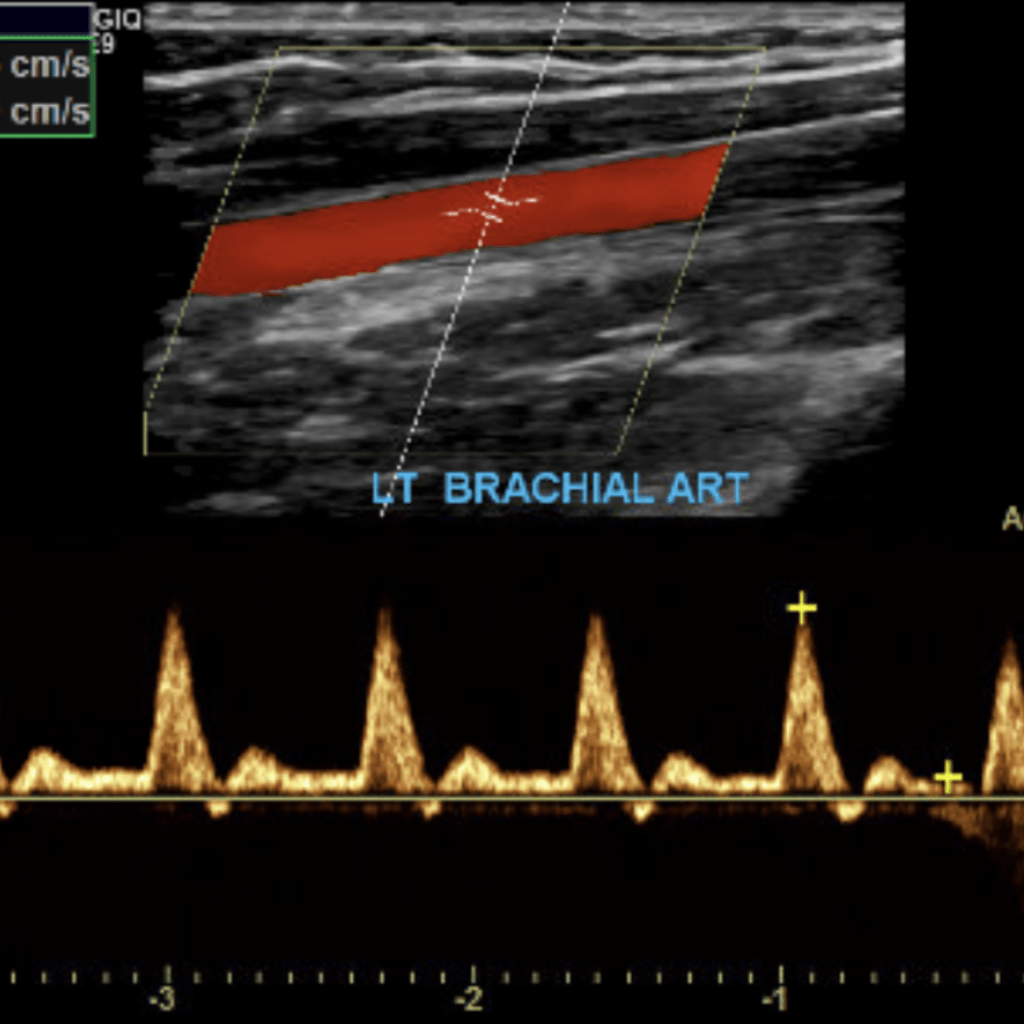

The subclavian artery arises from the brachiocephalic artery on the right and off of the aortic arch on the left. This artery further divides into the axillary, brachial, radial, ulnar, palmar and digital arteries respectively.